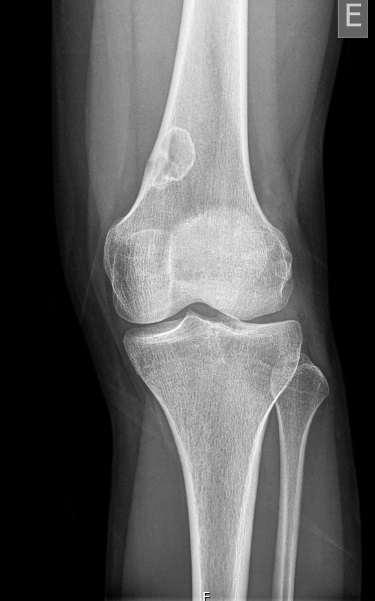

A 6-week-old male infant was brought to the emergency department with a three-day history of irritability, decreased food intake and a polymorphic skin eruption. He had no significant medical history, was exclusively breastfed with good weight gain. None of his family members had similar symptoms or lesions. The infant was in good general condition. Skin examination revealed an erythematous base with scattered vesicles, pustules and papules. The lesions were more prominent on the scalp, back and abdomen, including the neck, inguinal and axillary regions (Figure 1). Blood parameters were within reference ranges for age, with no increased inflammatory markers. Nevertheless, due to the exuberance of the lesions, a bacterial infection was suspected and intravenous flucloxacillin was initiated.

Figure 1A and 1B. Lesions in the torso: scattered vesicles, pustules, papules and nodules in an erythematous base.